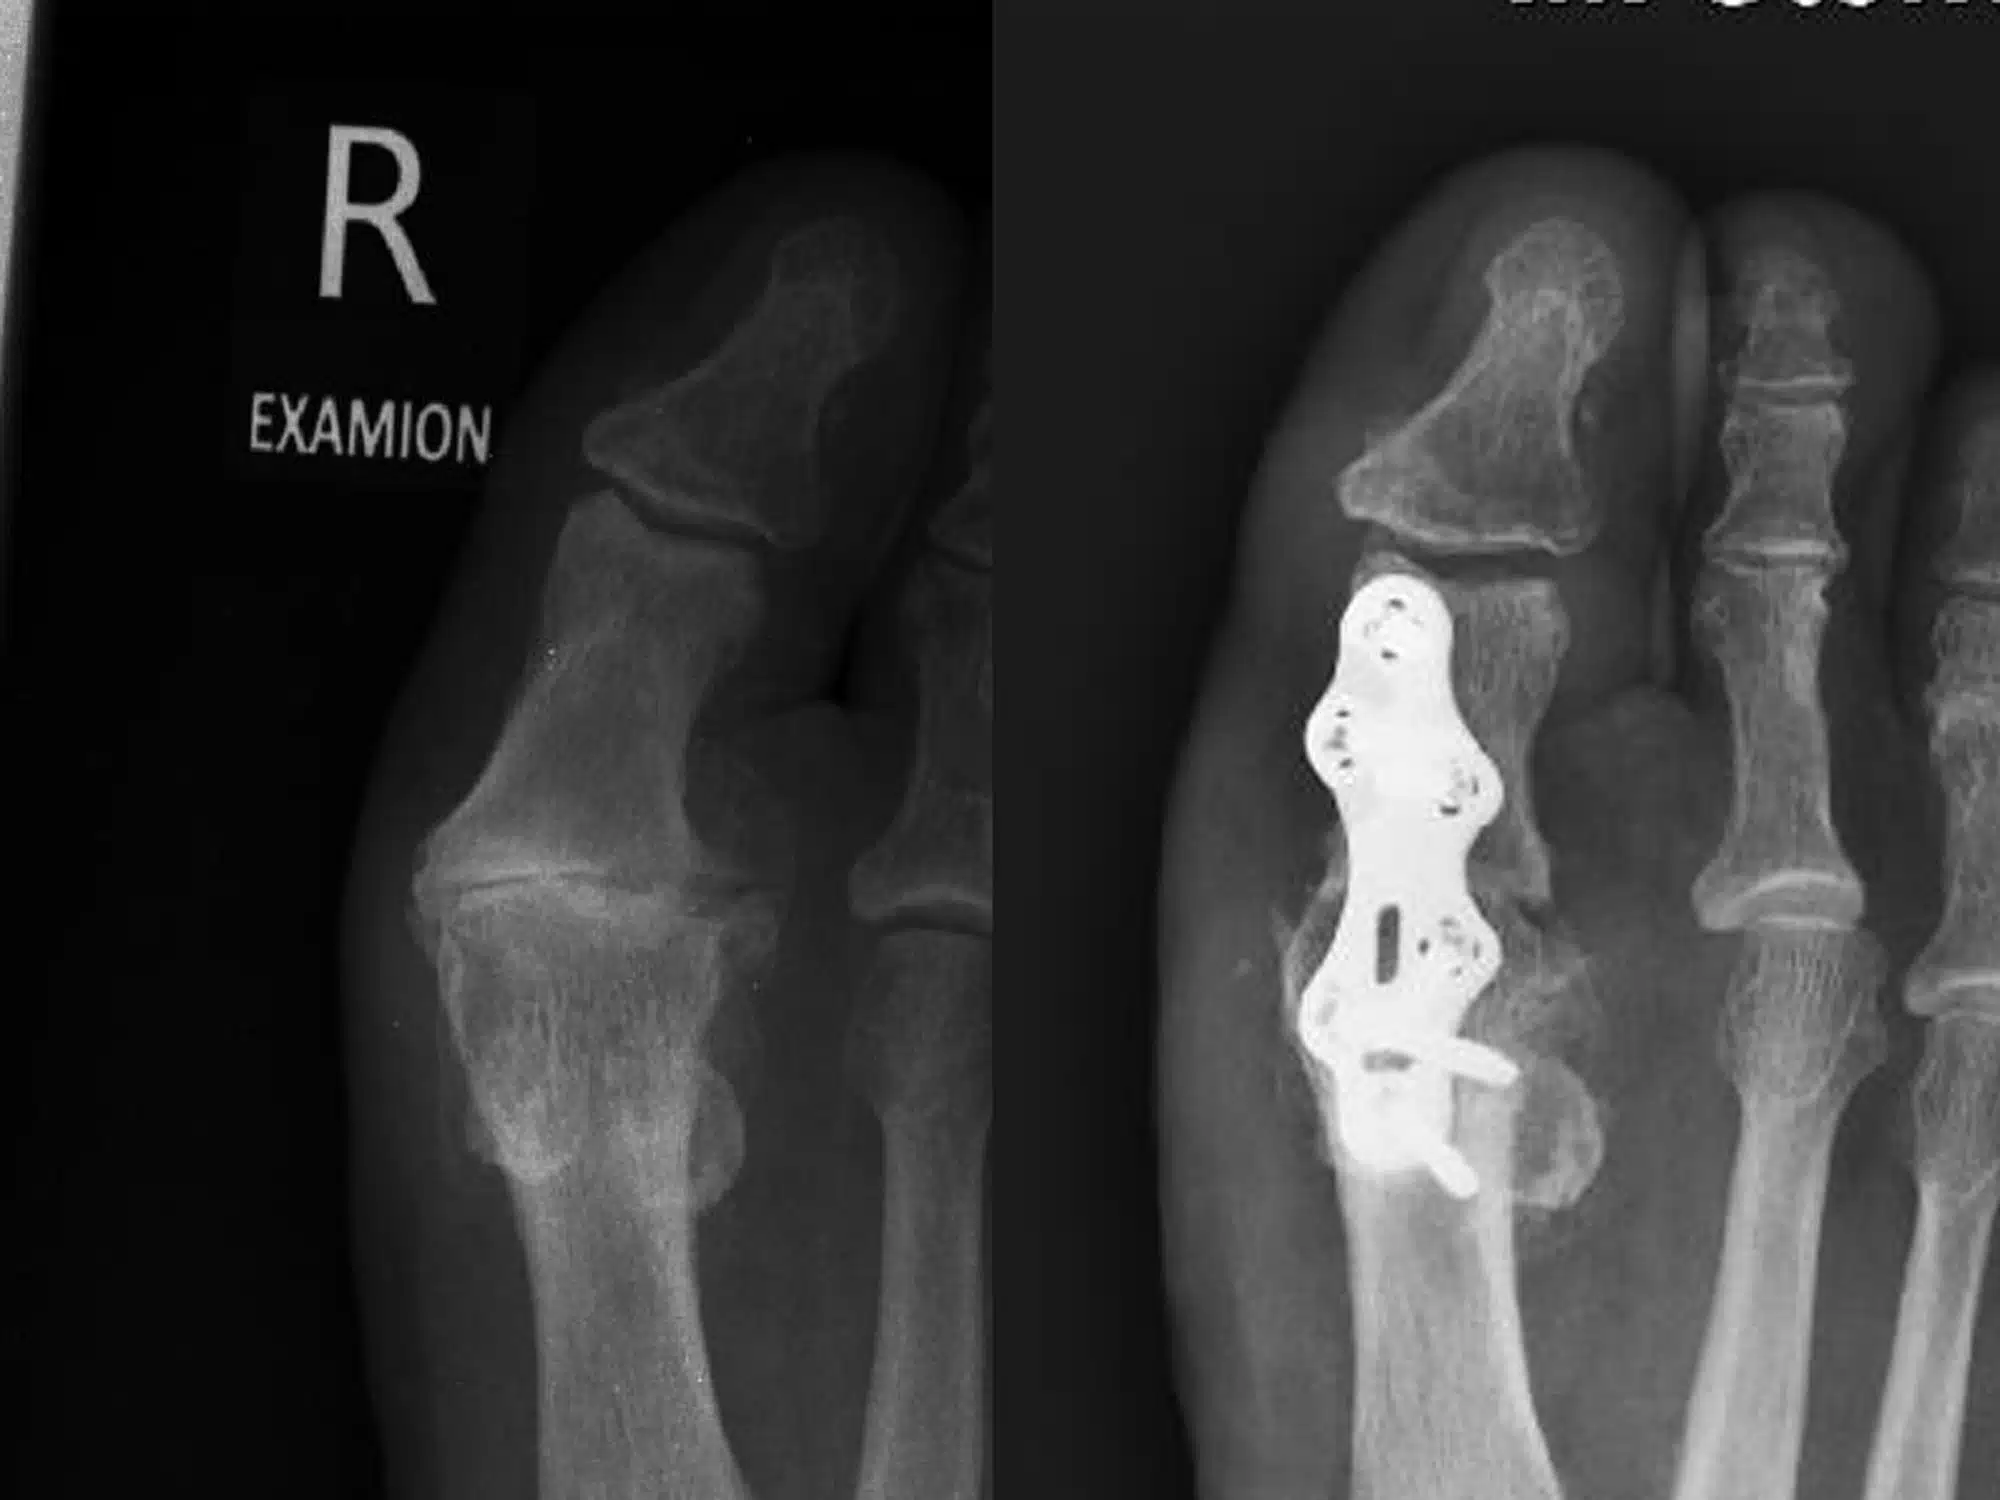

Bildgebung Befund (DP und seitlich, unter Belastung):

MTP-I: Ausgeprägte, überwiegend hypertrophe Arthrose. Der Gelenkspalt ist weitgehend aufgehoben, subchondrale Sklerosen an Metatarsalköpfchen und Grundphalanx, randständige osteophytäre Anbauten dorsal und medial; Metatarsalköpfchen verbreitert. Keine Frakturzeichen.

Strahlen II–V: Zeichen einer Zehenfehlstellung mit Tendenz zu Hammer-/Krallenzehen, jedoch ohne eindeutige luxatorische Fehlstellung der MTP-Gelenke. Weichteile unauffällig.

Vergleich:

Gegenseite mit schlankem Metatarsalköpfchen I und regelrechter Gelenkweite des MTP-I ohne osteophytäre Anbauten – dient als Referenz.

Beurteilung:

Bild eines fortgeschrittenen Hallux rigidus (MTP-I-Arthrose, KL 3–4) rechts mit nahezu aufgehobenem Gelenkspalt, subchondraler Sklerose und dorsomedialen Osteophyten.

Operation

Entscheidung zur Arthrodese des MTP‑I als Goldstandard bei endgradiger Arthrose. Osteophyten wurden entfernt; die Gelenkflächen in Cup‑and‑Cone‑Technik vorbereitet und das Gelenk in funktioneller Stellung (leichte Dorsalextension und Valgus) kompressionsstabil fusioniert. Fixation mittels zweier Kompressionsklammern. Hautverschluss mit Klammerpflastern, sodass keine Fadenentfernung notwendig war. Zusätzlich wurden konfliktierende Kleinzehen minimalinvasiv gelöst, parallel gestellt und für sechs Wochen getapet.

Unmittelbar postoperativ geringe Schwellung und Blutung; sichtbare Achskorrektur. Nach drei Monaten durchgehende knöcherne Fusion in korrekter Stellung, regelrechte Implantatlage; klinisch schmerzfrei, regelrechtes Abrollen über den Ballen, beschwerdefreies Tragen von Konfektionsschuhen. Zehen liegen nebeneinander ohne Überkreuzen; die zuvor laterale Hornhautbildung rückläufig.